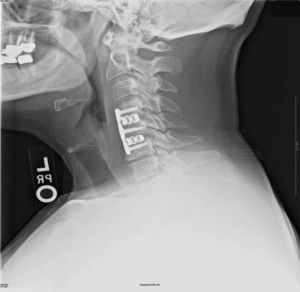

- Инструментарий: Задние шейные слияния могут быть дополнены специально разработанными фиксирующими устройствами, такими как скобки, винты, стержни и пластины. Эти устройства повышают стабильность и облегчают слияние.

Многие хирурги применяют фиксационные устройства (пластины с винтами) при переднем хирургическом доступе при выполнении ACDF или корпэктомии. Эти устройства помогают повысить стабильность при слиянии.

Импланты шейного отдела позвоночника на рентгене.